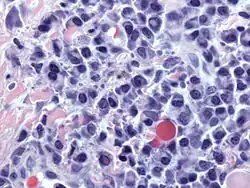

Plasmacytoma, H&E stain

Plasmacytoma, H&E stain -

Histopathology

A bone marrow biopsy is usually performed to estimate the percentage of bone marrow occupied by plasma cells. This percentage is used in the diagnostic criteria for myeloma. Immunohistochemistry (staining particular cell types using antibodies against surface proteins) can detect plasma cells that express immunoglobulin in the cytoplasm and occasionally on the cell surface; myeloma cells are often CD56, CD38, CD138, and CD319 positive and CD19, CD20, and CD45 negative.[21] Flow cytometry is often used to establish the clonal nature of the plasma cells, which will generally express only kappa or lambda light chain. Cytogenetics may also be performed in myeloma for prognostic purposes, including a myeloma-specific fluorescent in situ hybridization and virtual karyotype.

The plasma cells seen in multiple myeloma have several possible morphologies. First, they could appear like a normal plasma cell, a large cell two or three times the size of a peripheral lymphocyte. Because they are actively producing antibodies, the Golgi apparatus typically produces a light-colored area adjacent to the nucleus, called a perinuclear halo. The single nucleus (with a single nucleolus with vesicular nuclear chromatin) is eccentric, displaced by an abundant cytoplasm. Other common morphologies seen, but which are not usual in normal plasma cells, include:

- Bizarre cells, which are multinucleated

- Mott cells, containing multiple clustered cytoplasmic droplets or other inclusions (sometimes confused with Auer rods, commonly seen in myeloid blasts)

- Flame cells, having a fiery red cytoplasm[71][72]